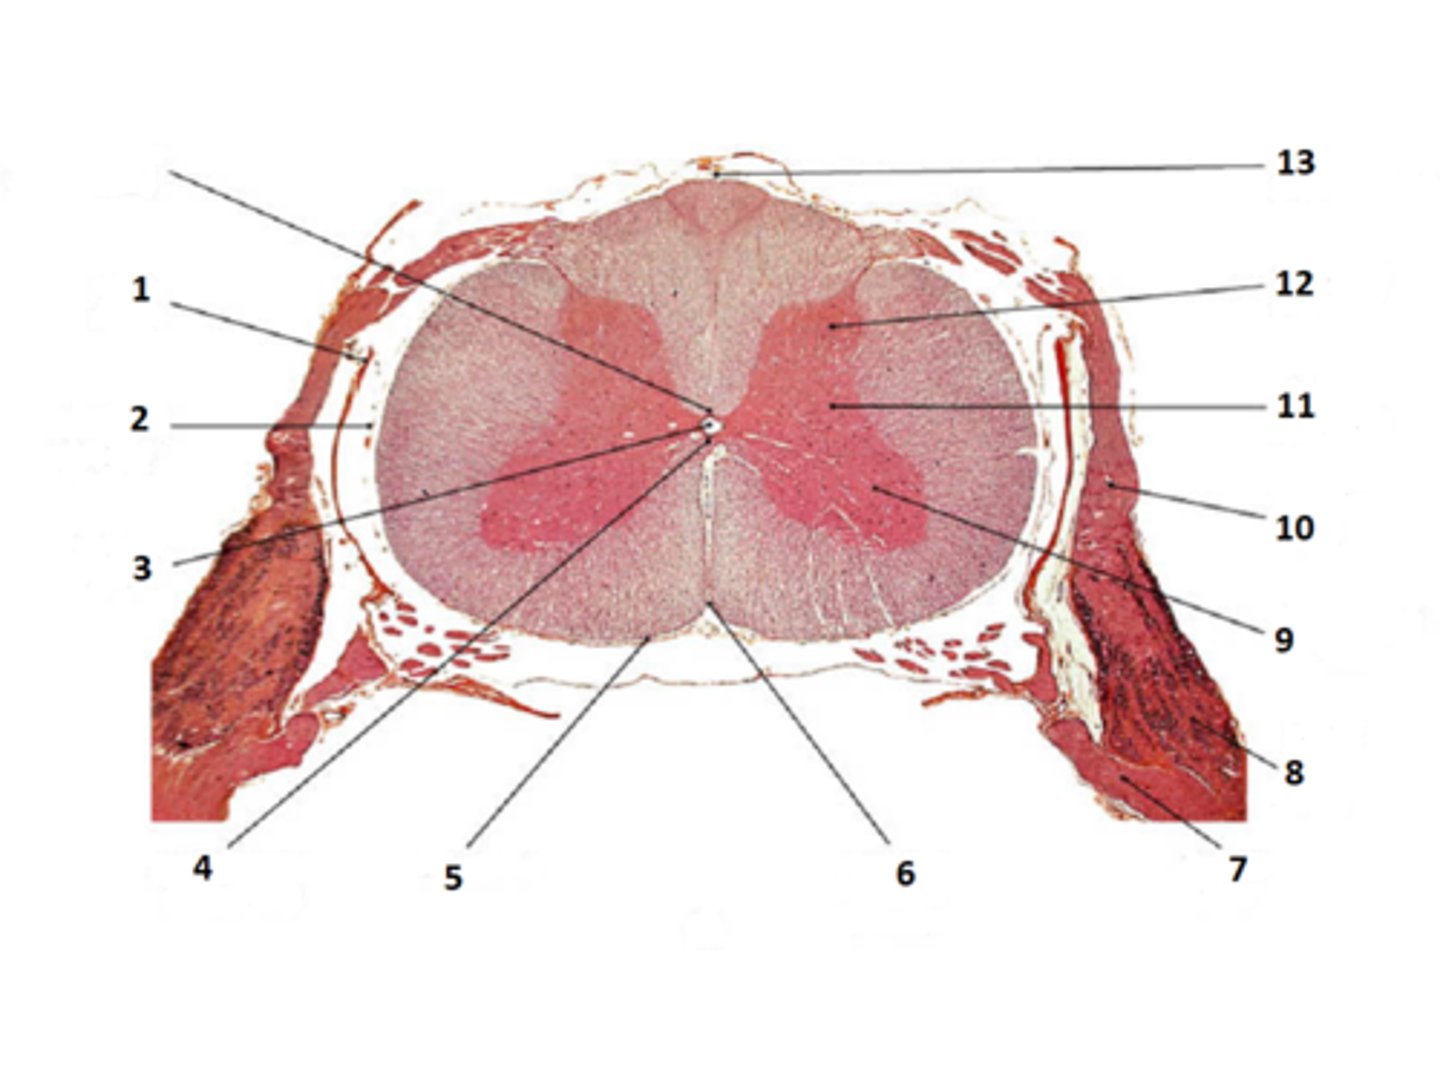

posterior gray horn

lateral gray horn

anterior gray horn

posterior white column

name 2

lateral white column

name 6

anterior white column

name 7

anterior median fissure

gray commissure

central canal

dorsal root of spinal nerve

ventral root of spinal nerve

dorsal root ganglia